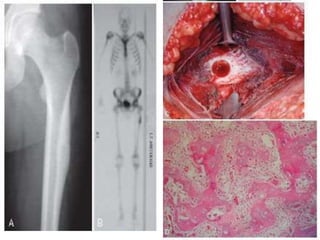

 Disorder of unregulated bone turnover

 Common in 5th-8th decades

 Slight male predominance

 Common sites – vertebral body, pelvis,

proximal femur

 Pathophysiology – excessive osteoclastic

resorption followed by increased osteoblastic

activity. Early lytic phase followed by

excessive bone production with cortical and

trabecular thickening

 Radiographically – depending on the stage of

the disease

Lytic phase – Bone resorption – “Blade of

grass” or “Flame” appearance from end of

bone towards diaphysis.

Later – bony sclerosis, thickened cortices and

trabeculae

 Bone scan - increased uptake, MRI

 Biopsy – Mosaic pattern with widened

lamellae, irregular cement lines and

fibrovascular connective tissue.

 1% - bone sarcoma - osteosarcoma